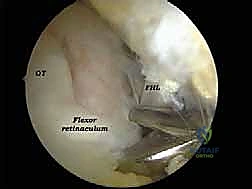

الخطوة 3: الاستكشاف البانورامي (Diagnostic Arthroscopy)

يتم إدخال كاميرا المنظار عالية الدقة (4K) عبر أحد المداخل، بينما تُستخدم الأدوات الجراحية الدقيقة في المدخل الآخر. تتيح الكاميرا للدكتور هطيف رؤية الهياكل الداخلية مكبرة عشرات المرات على شاشة عملاقة، مما يسمح بتقييم دقيق للمفاصل، الأوتار، والأربطة.

* تحرير وتنظيف وتر (FHL): إذا كان الوتر ملتهباً ومحاصراً، يتم قطع سقف النفق الليفي لتحريره، وإزالة الأنسجة الملتهبة (Tenosynovectomy) لضمان انزلاقه بحرية.